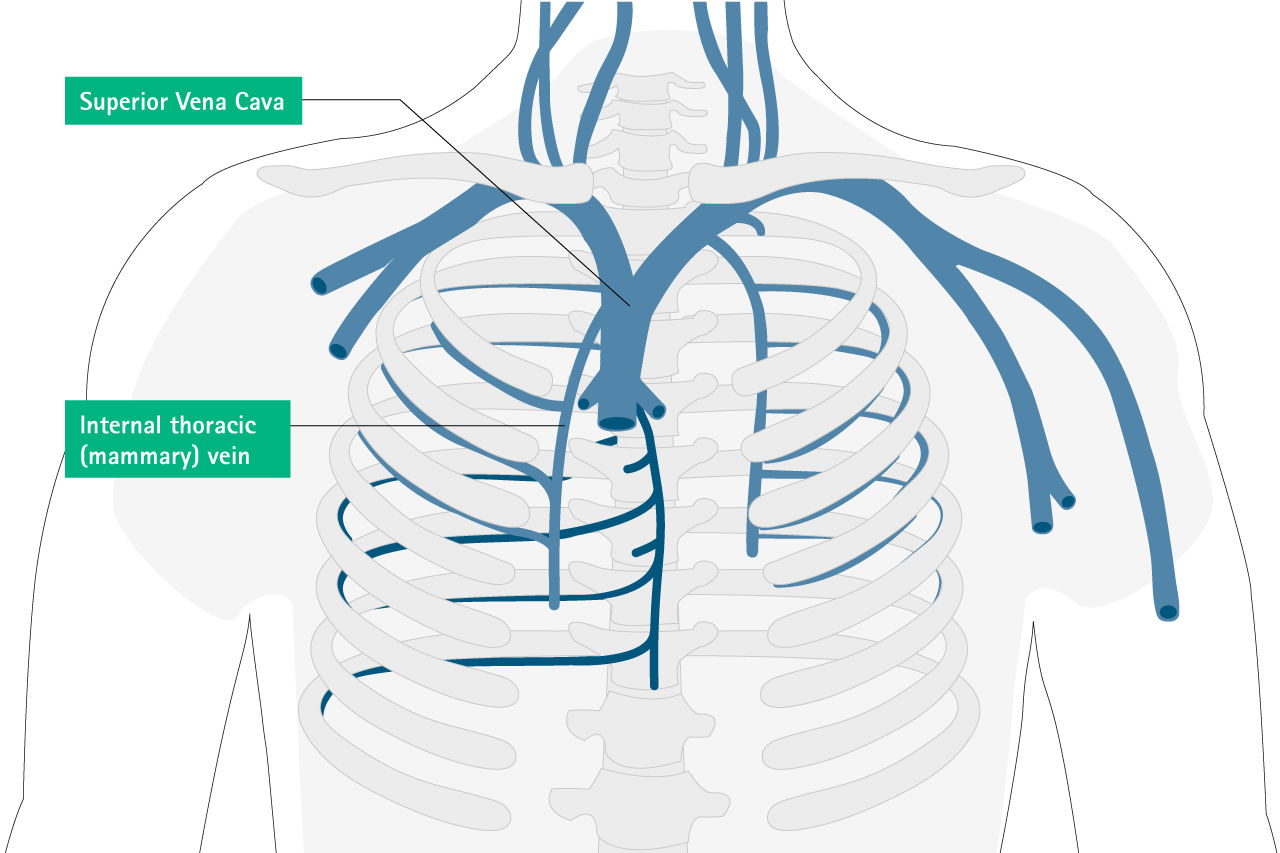

Intravascular Misplacement

Internal thoracic (mammarx) veinMediastinum